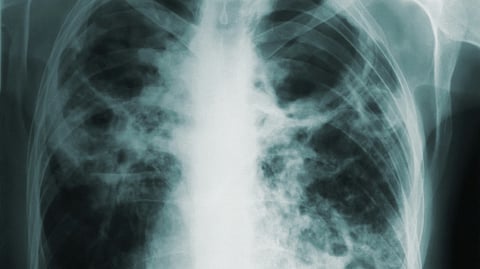

Tuberculosis (TB) is a contagious bacterial infection caused by Mycobacterium tuberculosis, primarily affecting the lungs but capable of spreading to other organs. It spreads through the air when a person with active pulmonary TB coughs, sneezes, or talks, releasing droplets that may be inhaled by others. The first-line treatment for TB includes Isoniazid, Rifampicin, Ethambutol, and Pyrazinamide. This regimen is called Directly Observed Therapy (DOTS).